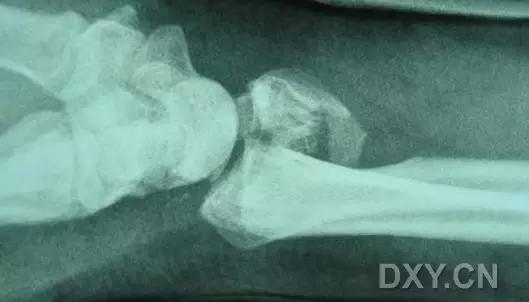

5. Hoffa 骨折

指股骨远端冠状面的骨折。

病例 1:一般股骨髁间、髁上粉碎骨折中含 Hoffa 骨折的不少见,但单纯后髁骨折则很少见。

正位片

侧位片

水平位 CT

第 2 例

第 3 例